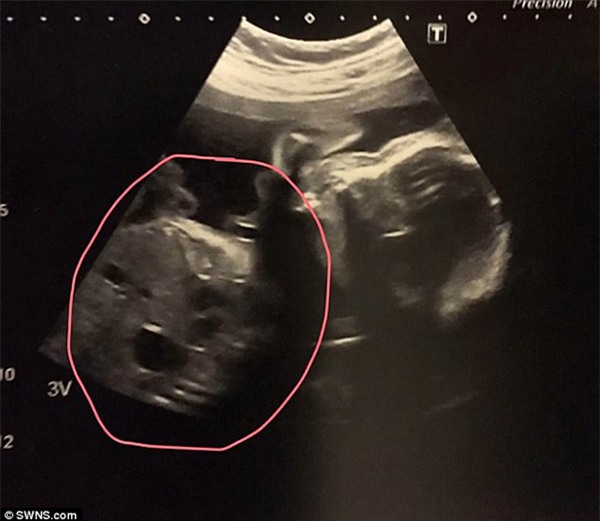

Hình ảnh siêu âm thai của con khiến cặp đôi sốc nặng vì có khuôn mặt của chú chó.

Qua bức ảnh siêu âm thai này, có thể thấy khuôn mặt em bé khá rõ rệt, trong khi phần bụng và nội tạng lại tạo thành một khuôn mặt khác giống như một chú chó săn còn tay chân của bé lại tại thành tai của chú chó.